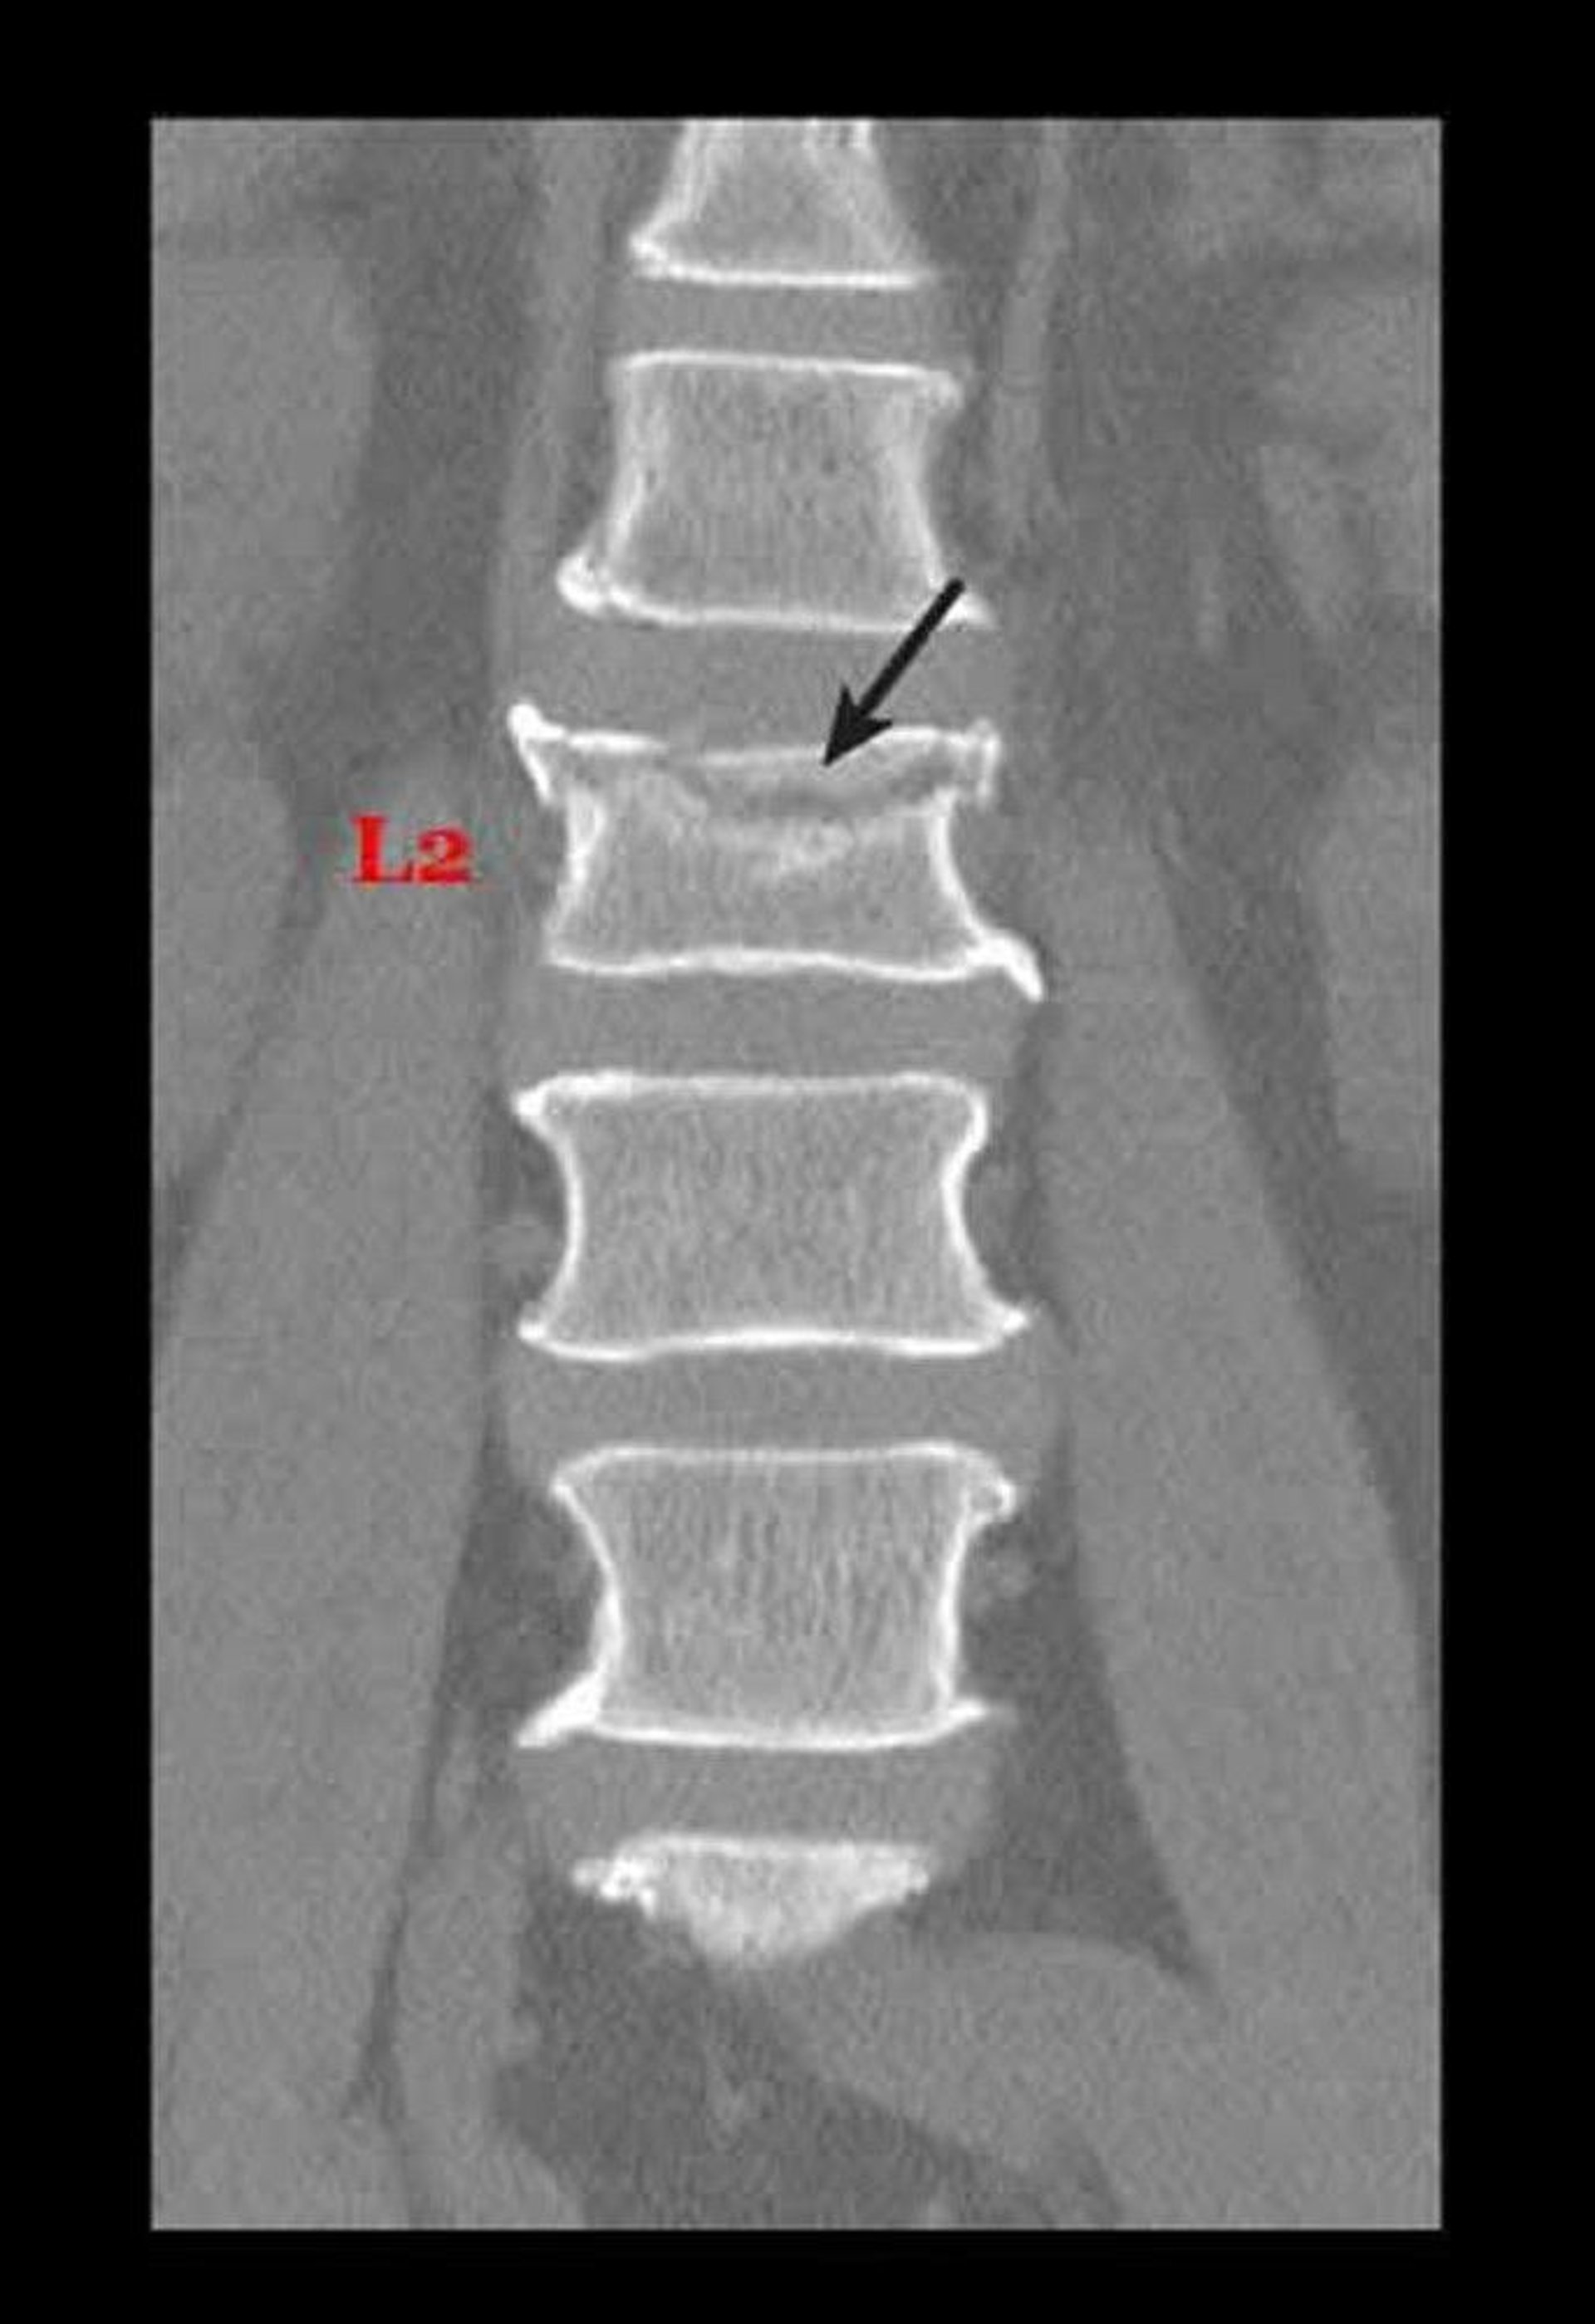

Fraktur Kompresi Karena Osteoporosis

Garis gelap di bawah panah mewakili fraktur tulang punggung lumbar (di punggung bawah). Tulang punggung ini terkompresi, sehingga terlihat lebih pendek daripada biasanya.